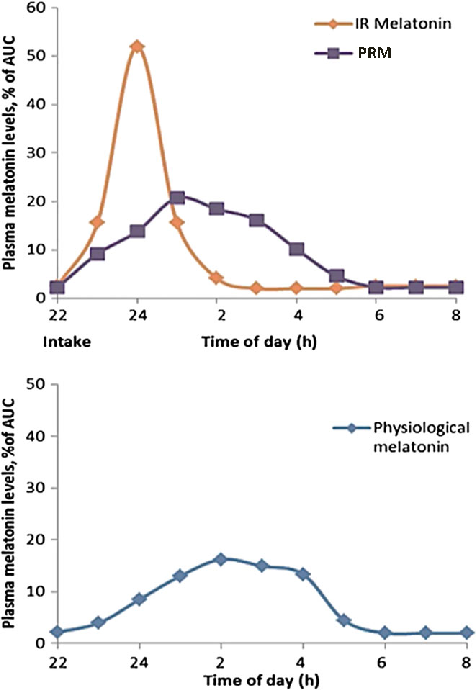

Exogenous melatonin administration influences circadian phase positioning, with the direction and magnitude of phase shifts depending on the timing of administration. Evening doses advance the circadian clock, while morning doses may cause phase delays.

Clinical applications of melatonin extend beyond sleep induction to include circadian rhythm resynchronization in jet lag, shift work disorder, and delayed sleep-wake phase disorder. Dose-response relationships vary across these conditions.